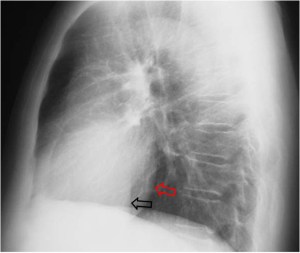

SIGNO DEL CASQUETE APICAL IZQUIERDO

La aparición de una densidad en el ápex pulmonar izquierdo, de borde inferior cóncavo y bien delimitado (casquete apical) en un paciente con traumatismo torácico, debe hacernos sospechar la existencia de una rotura aórtica.

Deben excluirse otras causas de casquete apical, especialmente las lesiones residuales tuberculosas, que suelen acompañarse de otros hallazgos como tractos fibrosos pleuro-parenquimatosos, pérdida de volumen en el lóbulo superior, granulomas, etc.

Mostramos un caso de rotura aórtica por accidente de moto. En este paciente también aparece el signo de la alteración del contorno aórtico.

En el corte de TC de tórax con contraste intravenoso del mismo paciente vemos la rotura aórtica (flecha verde), un hemotórax bilateral –algo más cuantioso en el hemitórax izquierdo- (flechas azules) y un hematoma mediastínico (flecha naranja).